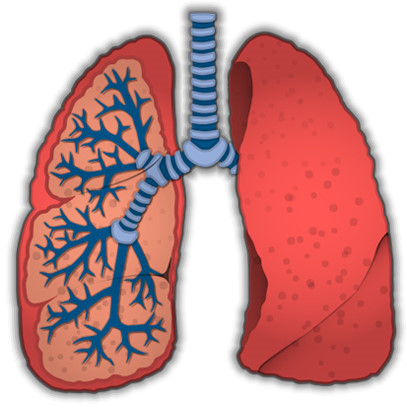

폐암은 암세포가 커지거나 주변 기관으로 전이되면서 다양한 증상을 유발합니다. 증상이 나타났을 때는 이미 어느 정도 진행된 경우가 많으므로, 아래 증상들을 주의 깊게 살펴봐야 합니다. 다음은 폐암 환자들이 흔히 겪는 10가지 주요 초기 증상입니다.

- 반복되는 폐렴 또는 기관지염

- 설명: 폐암 세포가 기관지를 막아 공기 순환을 방해하면 그 뒤에 있는 폐 조직에 세균 감염이 발생하기 쉽습니다. 이로 인해 폐렴이나 기관지염에 자주 걸리거나, 항생제 치료에도 잘 낫지 않는 증상이 나타날 수 있습니다.